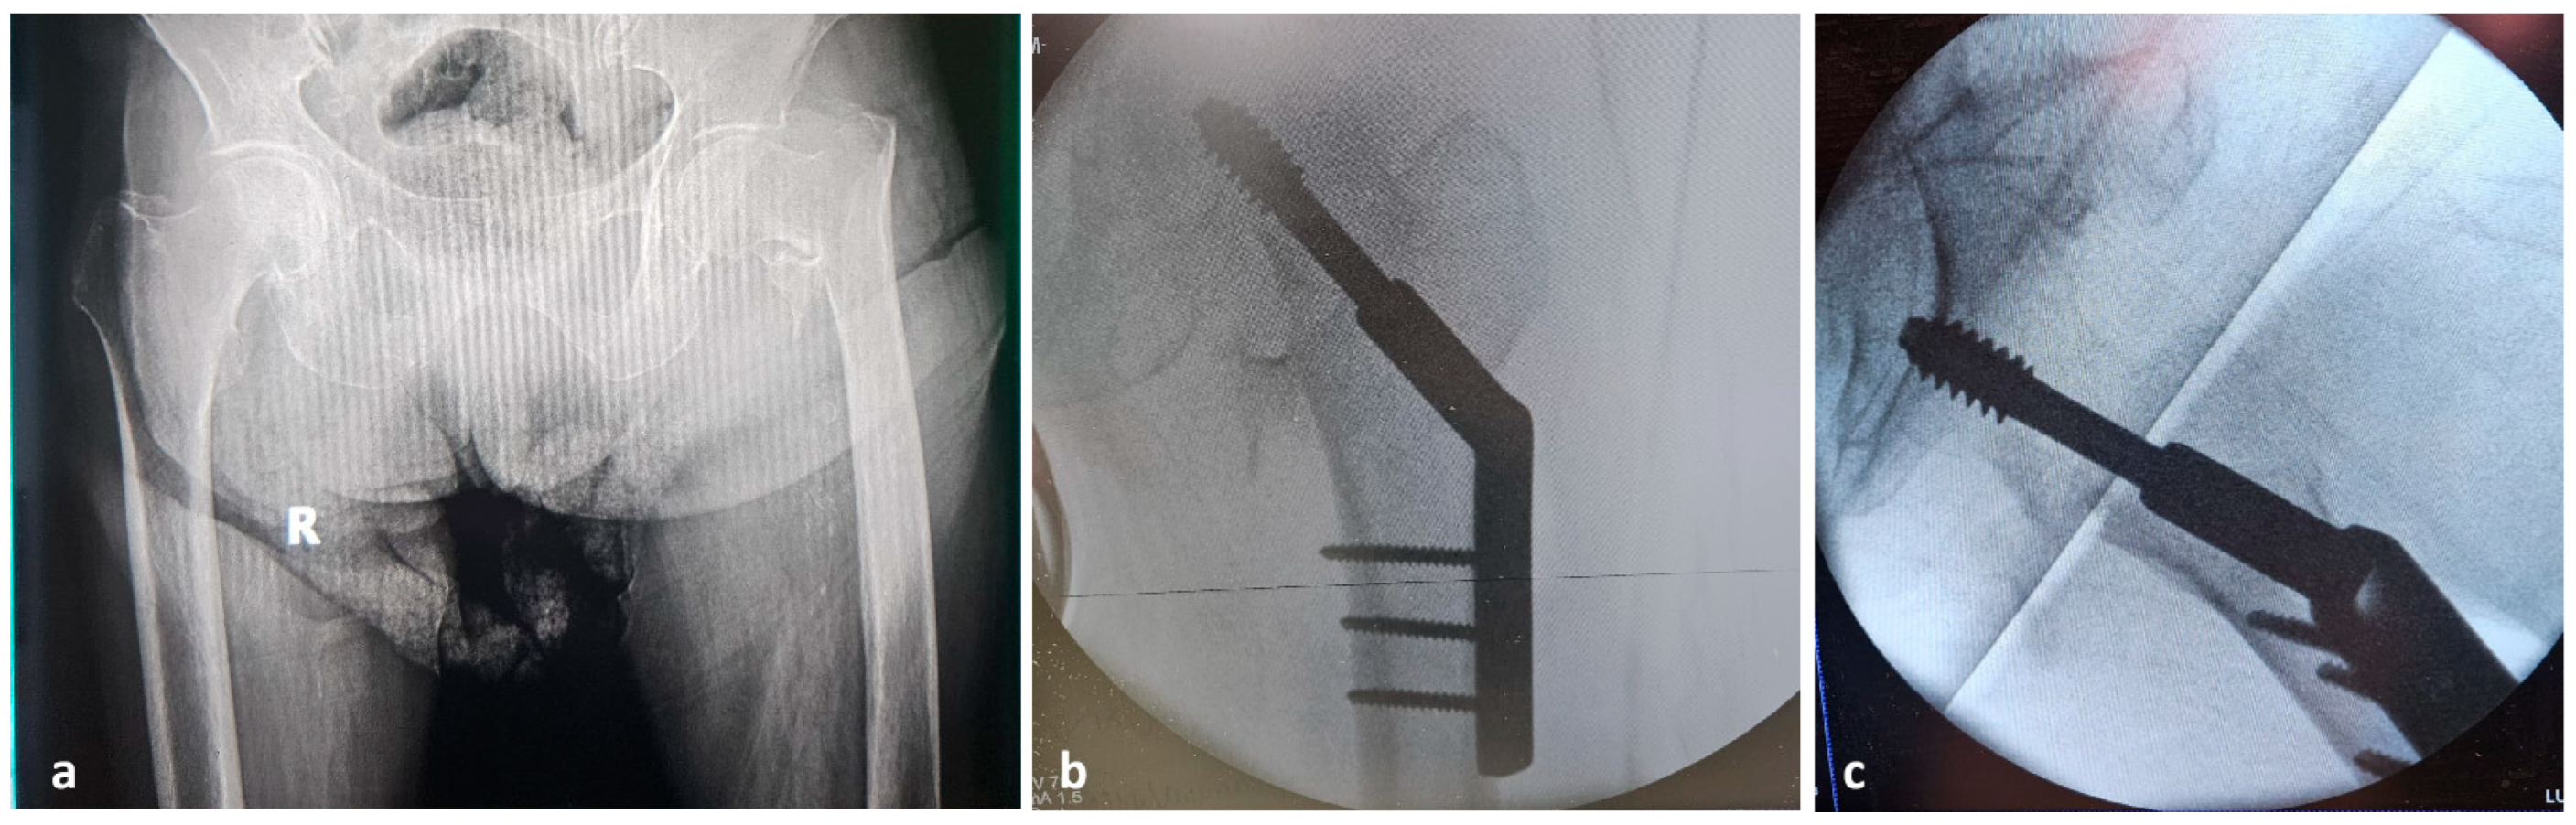

2. Case Presentation